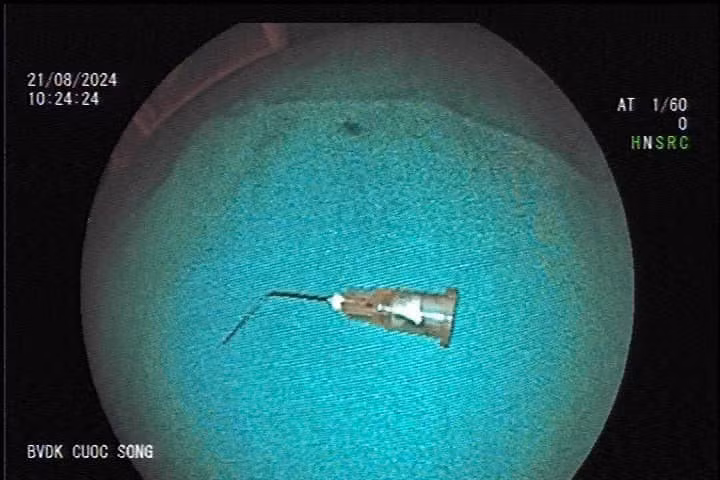

Các bác sĩ tiến hành gây mê nội soi phát hiện mũi kim nằm trong lòng dạ dày. Dị vật là kim tiêm loại bơm 5ml bẻ cong. Rất may, dị vật chưa đâm thủng thành dạ dày.

| Mũi kim được gắp ra từ dạ dày của bệnh nhân. Ảnh BVCC |